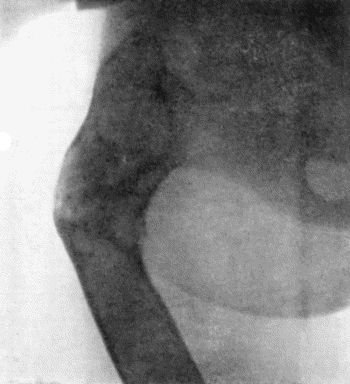

| 49. | Zanthoma of Buttock | 189 |

| 50. | Chondroma growing from Infra-Spinous Fossa of Scapula | 190 |